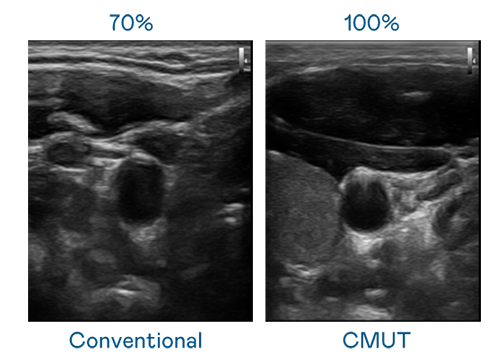

CMUT 技術是一種用電容式微機電元件來產生超音波訊號的技術。與傳統 PZT 壓電式技術相比,CMUT 頻寬增加 30%,更寬頻的超音波訊號讓影像解析度大幅提升,是實現高影像品質醫療超音波掃描、促進精準醫療發展的關鍵技術。

超音波影像的解析度高低,首先取決於探頭能發出的訊號頻寬。爱游戏体育网页登录 CMUT 可提供高清晰的超音波訊號,提供高頻寬、高靈敏度、影像紋理細節更高的超音波影像,協助醫護人員縮短影像判讀時間及利用精準的醫療影像進行診斷。